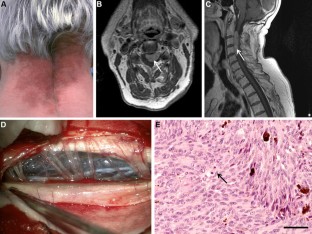

Küsters-Vandevelde, H.V.N., Germans, M.R., Rabbie, R. et al. Whole-exome sequencing of a meningeal melanocytic tumour reveals activating CYSLTR2 and EIF1AX hotspot mutations and similarities to uveal melanoma. Brain Tumor Pathol 35, 127–130 (2018). https://doi.org/10.1007/s10014-018-0308-1